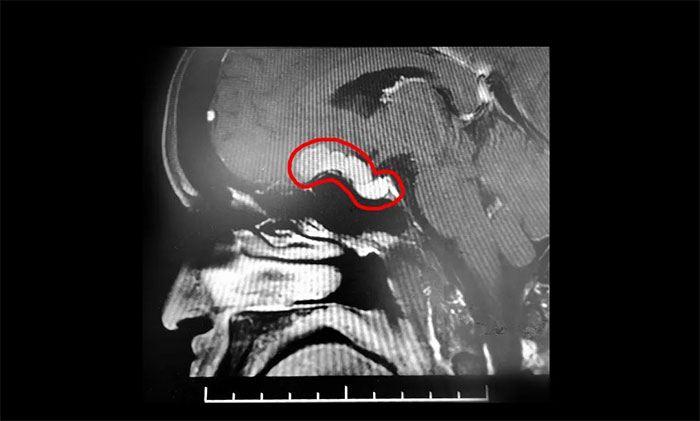

入院檢查顯示,左眼視力下降,外側視野缺損。鞍區(qū)MRI平掃+增強顯示,鞍上可見類橢圓形異常信號,大小約2.8cm*1.5cm,與垂體分解分界清晰,與視交叉、海綿竇分界欠清晰。

▲ 腫瘤向鞍上生長